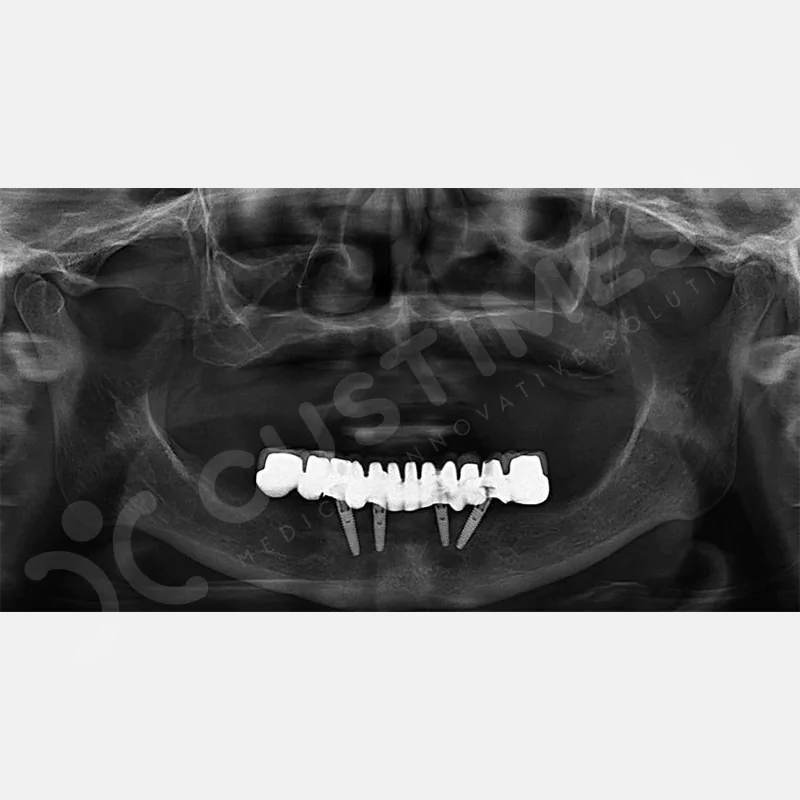

VAKA 1

VAKA 2

VAKA 3

VAKA 4